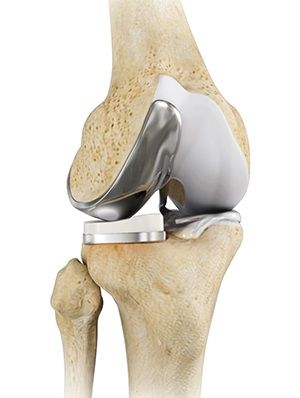

• Total Knee Replacement

Total Knee Replacement

Total knee replacement, also called total knee arthroplasty, is a surgical procedure in which...